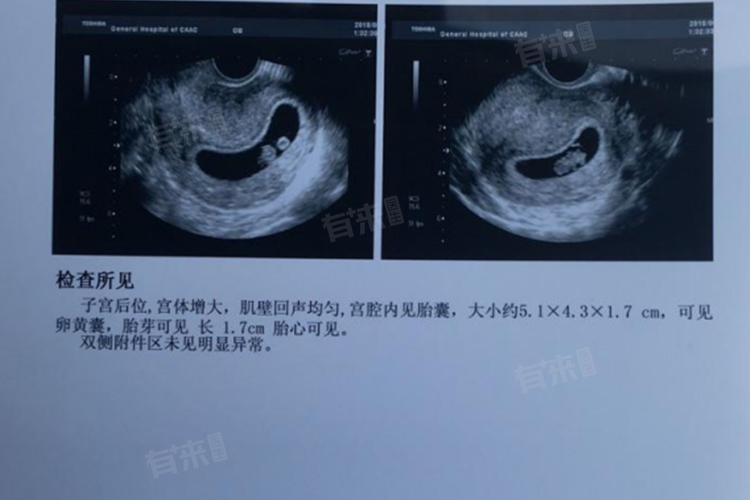

2、超声检查推测法:在怀孕早期,尤其是对于月经不规律的女性,超声检查是较为准确的方法,通过测量孕囊大小、胎儿头臀长等指标,医生可以根据相关公式推算出怀孕的大致周数,进而换算成怀孕月份,不同阶段的超声指标推算精度有所差异。